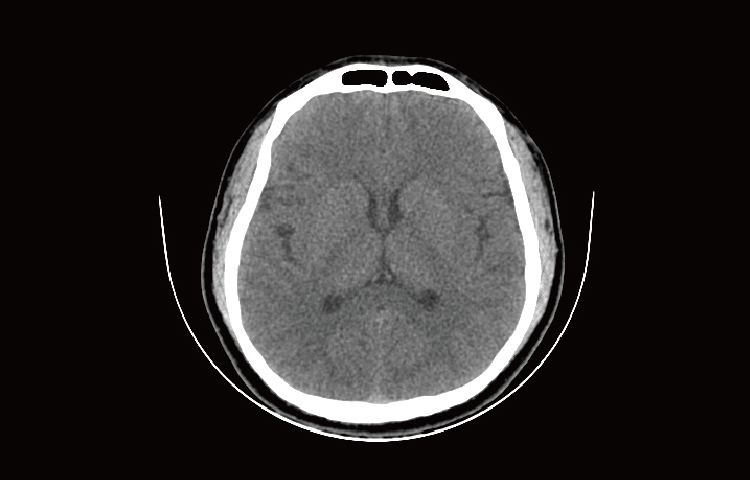

Скриншоты снимков